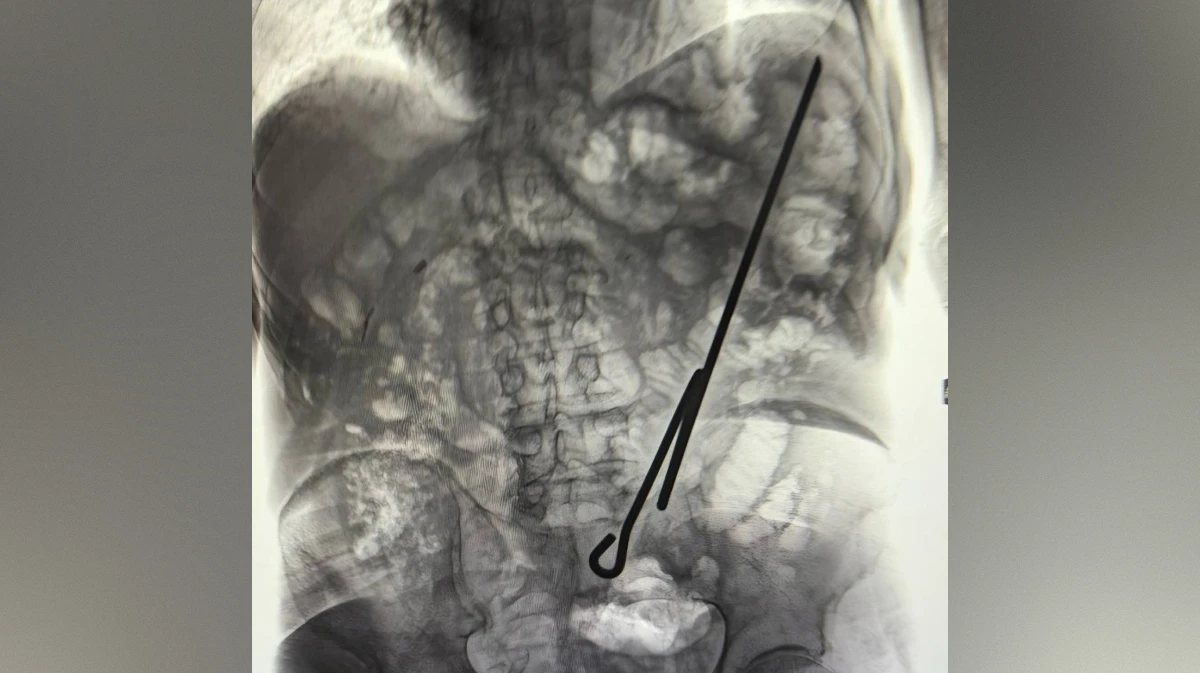

Первый случай был связан с 84-летним мужчиной, который при выполнении домашней работы напоролся на самодельный инструмент. Врачи провели обследование и прооперировали пациента. К счастью, ни один орган пожилого мужчины не был поврежден, так как пациент был голоден.